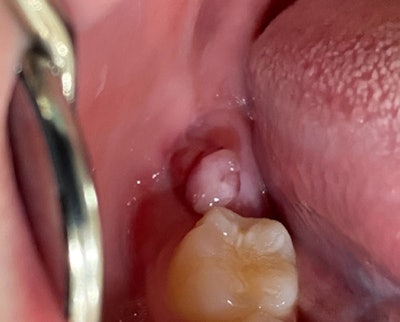

12-year-old girl with a mandibular lesion

A 12-year-old girl presented to the pediatric dentist's office. She was referred by her family dentist because of a "bump" on the right posterior mandible, distal to tooth #30. The patient said that the lesion had been there for at least six months. The intraoral examination revealed a soft, painless, red, pedunculated, lesion over the posterior right alveolar ridge, distal to tooth #30.